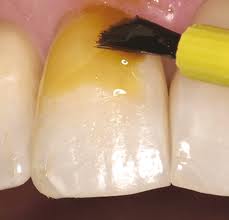

APLICAÇÃO TÓPICA DE FLÚOR (ATF)

É um procedimento preventivo que tem como objetivo fortalecer os dentes que apresentam risco de cárie. A aplicação do flúor pode ser realizada de diversas formas, entre elas, aplicação direta nos dentes, bochecho e na forma de gel ou espuma, através de moldeiras ajustáveis, deixando o flúor em contato com a superfície dental num período de 2 a 4 minutos. O flúor também pode ser aplicado sob os dentes na forma de verniz. Essa forma de aplicação é mais recomendada para pacientes muito jovens que não toleram o uso de moldeiras. Após a aplicação é necessário ficar pelo menos 30 minutos sem ingerir alimentos ou líquidos.